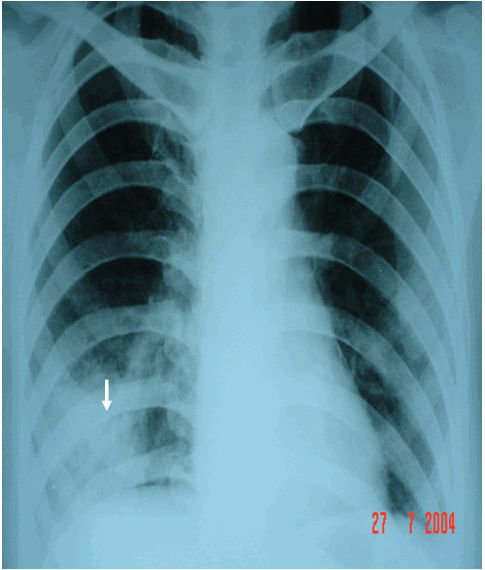

Áp xe đáy phổi phải có dạng đám mờ trên phim phổi thẳng

Trên đây là một số thông tin liên quan đến bệnh Áp xe đáy phổi phải có dạng đám mờ trên phim phổi thẳng, hy vọng sẽ giúp các bạn có thêm những hiểu biết cần thiết trong quá trình thăm khám và chẩn đoán bệnh!